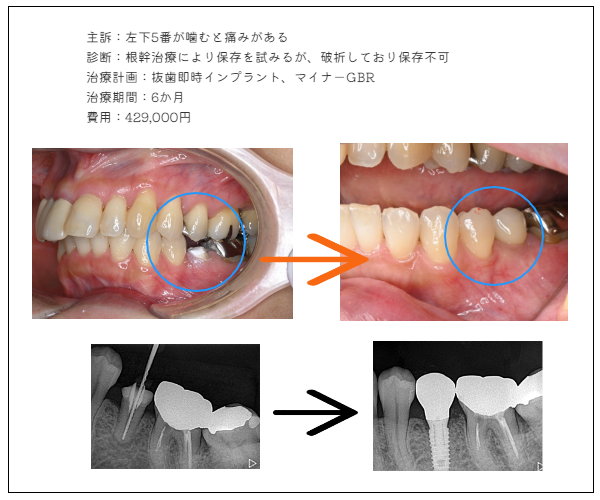

imprant症例1

MYデンタル審美歯科